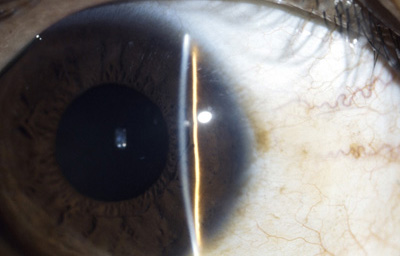

Deformación del plano del Iris, sospecha

Archivo Fotográfico Dr. Francisco Barraquer

Quiste en el epitelio pigmentario de la cara posterior del Iris

Archivo Fotográfico Dr. Francisco Barraquer